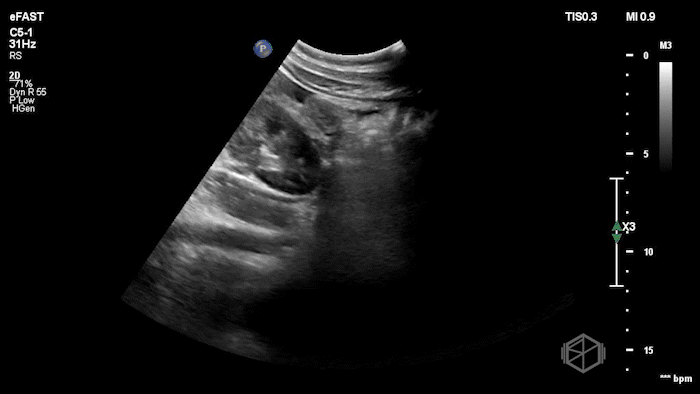

Drs. Ariz and Scavelli were caring for an approximately 40-year-old woman, G2P1, at approximately 8 weeks gestation, who presented to the ED with abdominal cramping. She was hypotensive on arrival, prompting the team to reach for the ultrasound immediately. They saw the following:

POCUS showed free fluid throughout the abdomen, including the RUQ, LUQ, and pelvis. The uterus was empty, and the final clip appears to show a complex left adnexal mass.

Diagnosis: Left ectopic pregnancy with hemoperitoneum